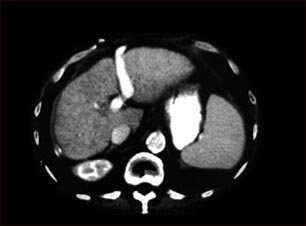

Cirrosis hepática; TC

TC del abdomen superior mostrando cirrosis hepática.